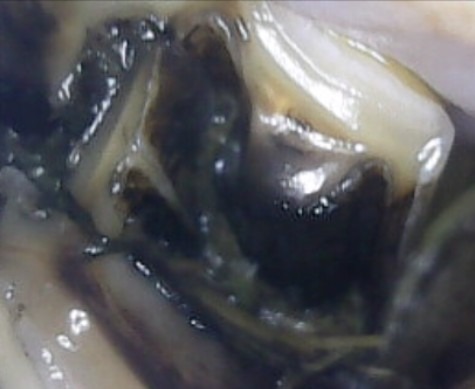

Infundibulumin karies, luokka 3

Luokan 2 karieksesta kolmosluokaan muuttuva karies. Karies on alkanut värjätä kiilteen ulkopuolella olevaa dentiiniä tummaksi. Tällainen reikä saattaa aiheuttaa kipua ja altistaa myöhemmin suurentuessaan hampaan halkeamiselle. Tällaisen reiän paikkaamista suositellaan. Hampaan paikkauksia tehdään hampaisiin erikoistuneilla klinikoilla.